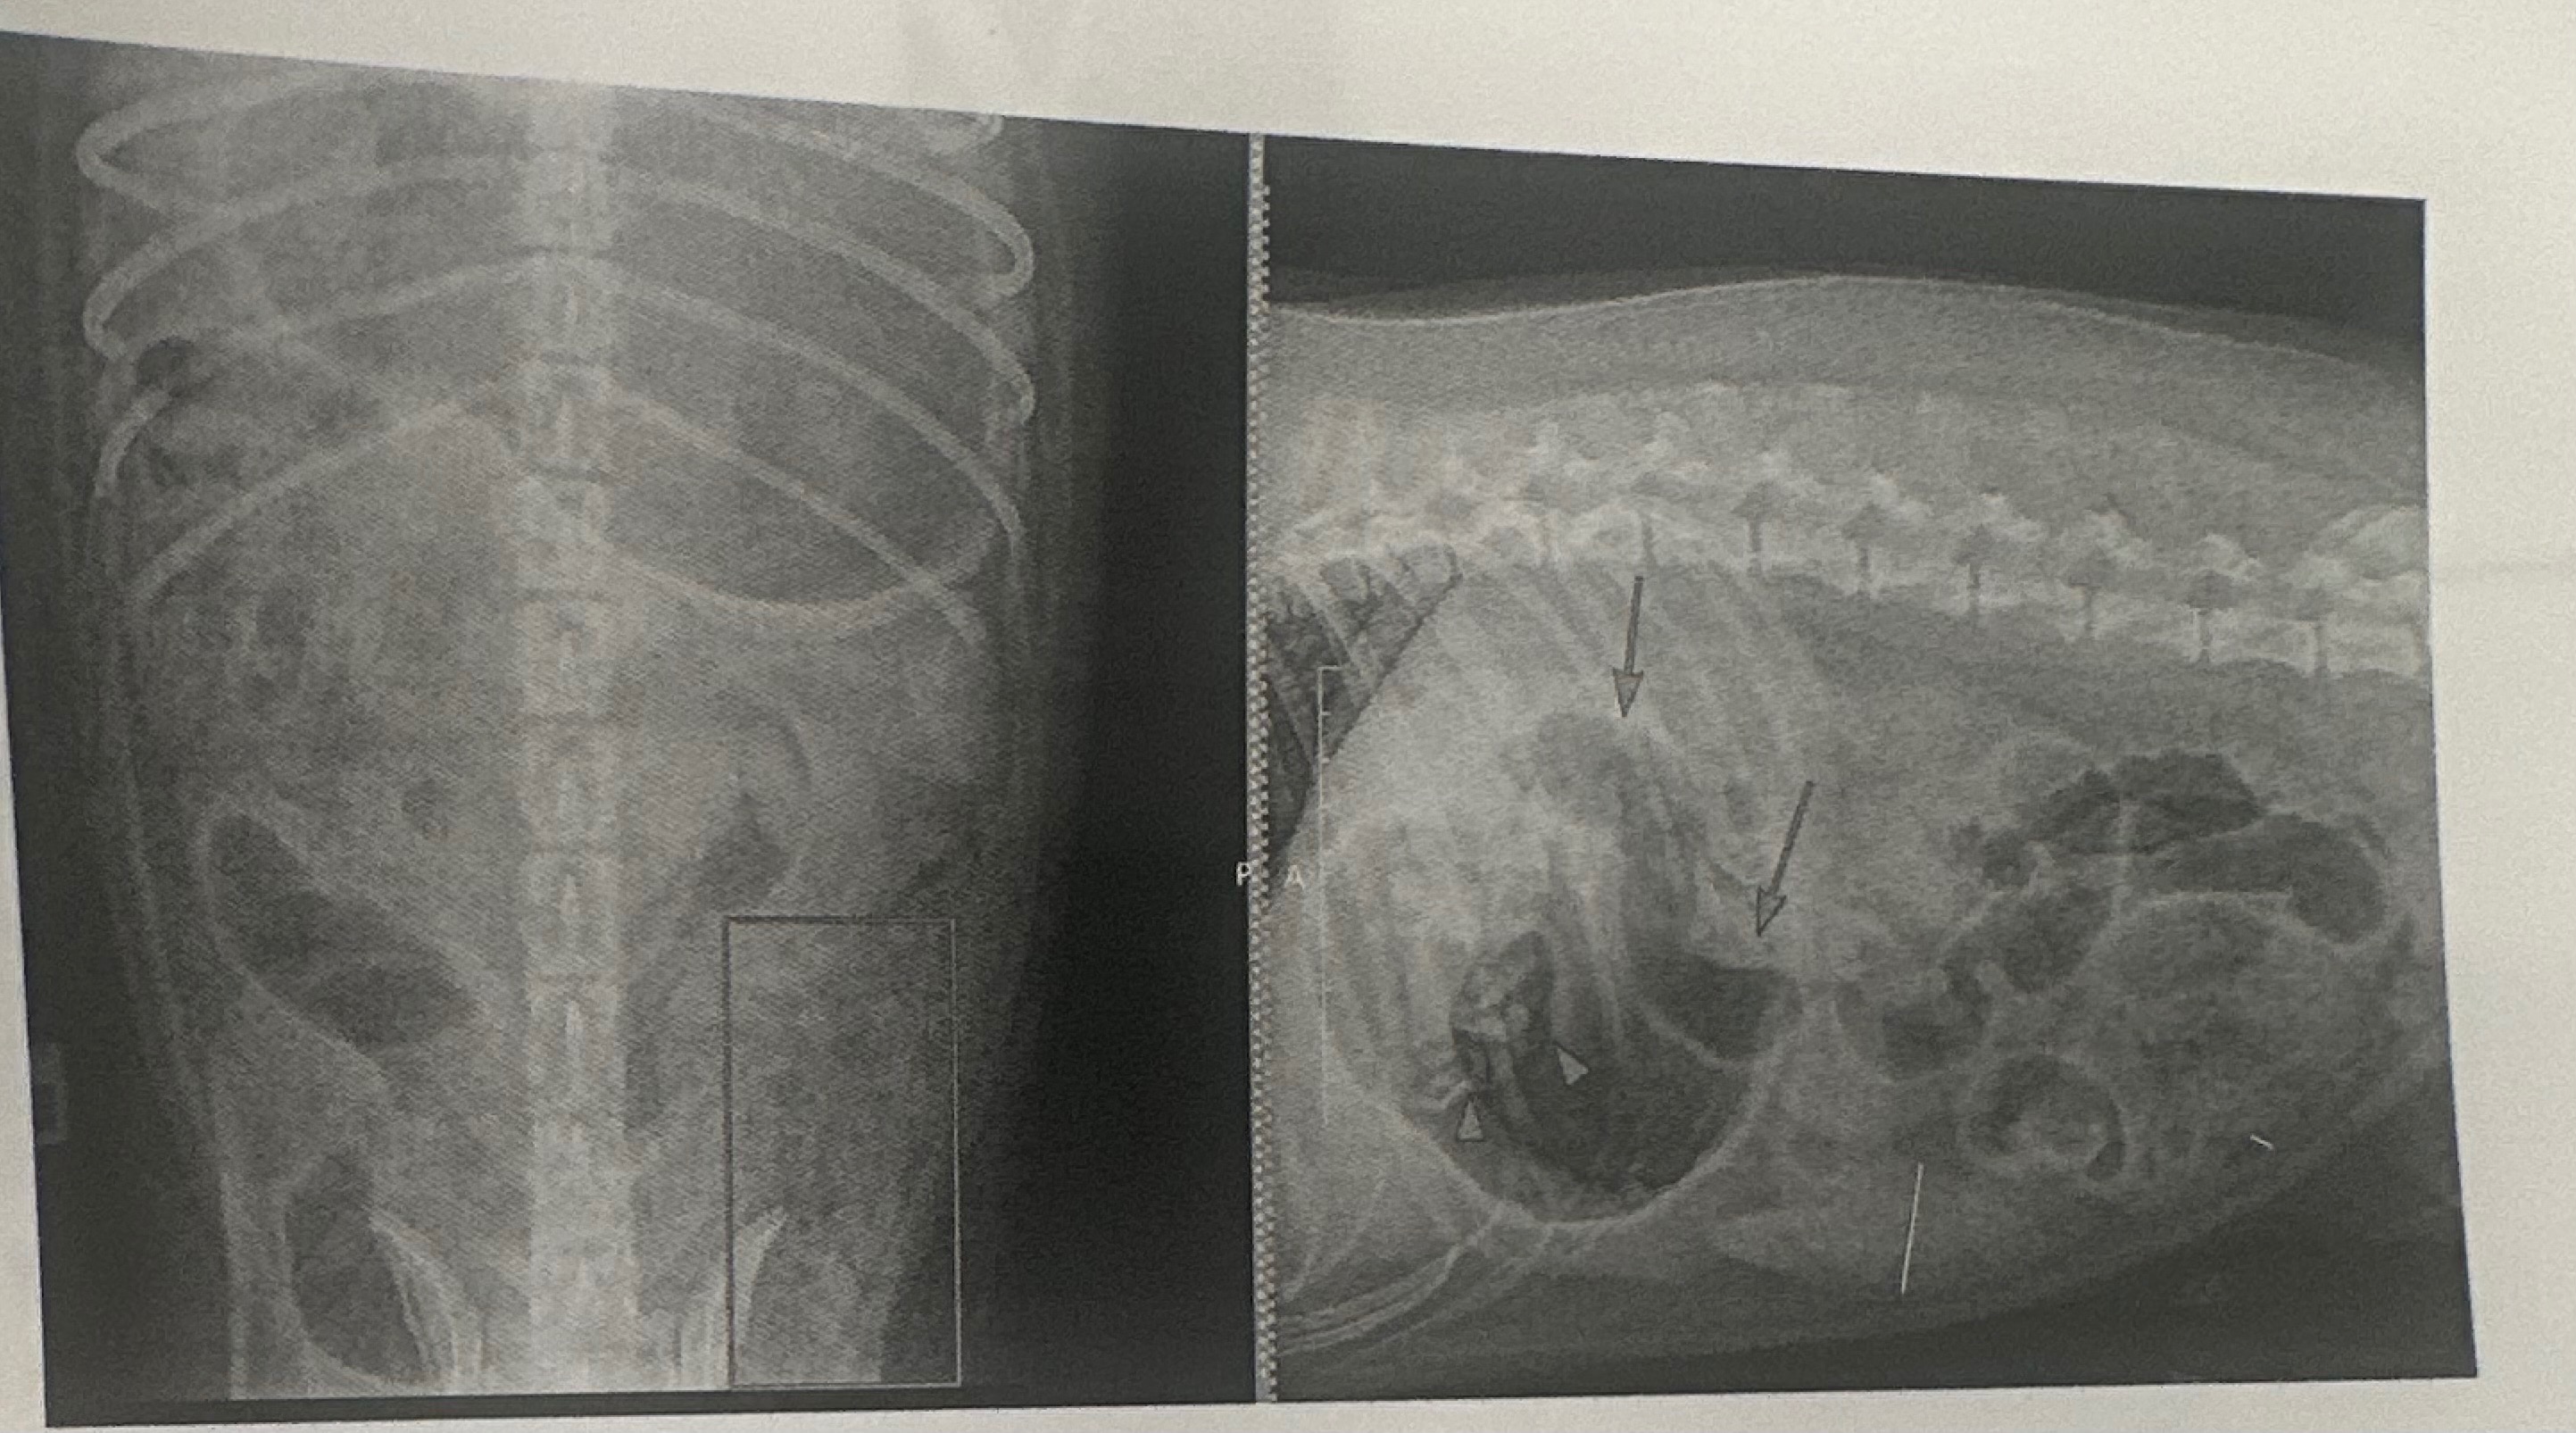

My sweet dog Hunter recently went through a serious health emergency and had to undergo stomach surgery. It was a scary and emotional experience, but Hunter is a fighter and is now on the road to recovery.